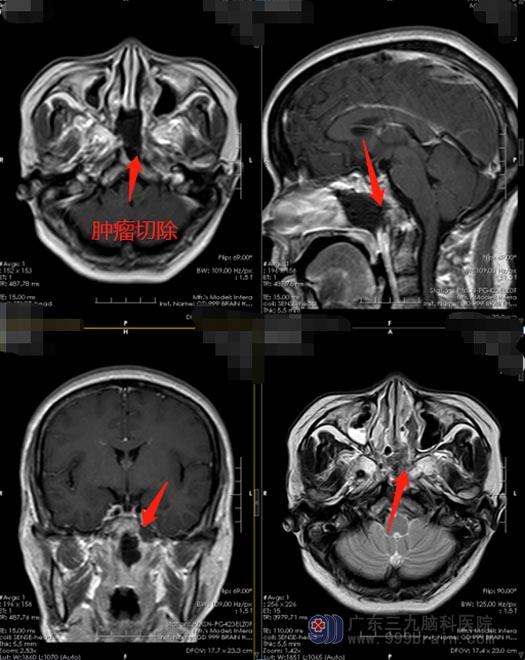

11-13日,小刘在内镜下经鼻行斜坡、鼻咽部复发脊索瘤切除术。木后恢复良好,左耳听力恢复明显,复查MR显示:肿瘤全切,一周后即办理了出院。

▲术后